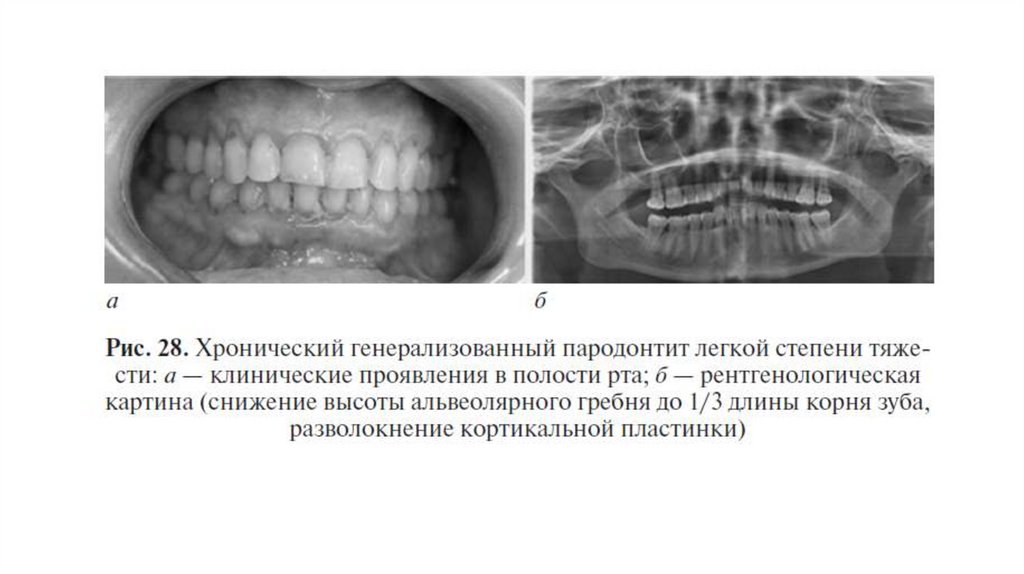

Легкая степень

Воспалительная резорбция кортикальной пластинки на вершине

межальвеолярной

перегородки

и

/или

снижение

высоты

межальвеолярной перегородки на 1/3 длины корня зуба. Потеря

клинического прикрепления до 4 мм. Подвижности зубов нет.

• Легкая степень тяжести ХП: степень потери прикрепления до 4 мм (глубина пародонтального кармана до 3 мм плюс

рецессия десны); резорбция костной ткани межальвеальвеолярных перегородок до 1/3 длины корня. Патологической

подвижности зубов нет, их смещение не выражено.